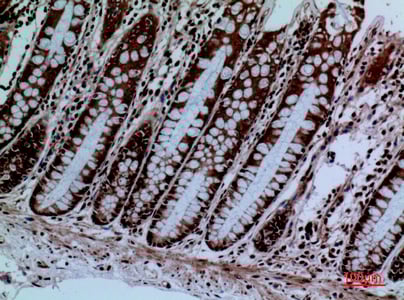

IHC (Immunohiostchemistry)

(Formalin-fixed and paraffin-embedded human cancer tissue reacted with the primary antibody, which was peroxidase-conjugated to the secondary antibody, followed by DAB staining. This data demonstrates the use of this antibody for immunohistochemistry; clinical relevance has not been evaluated. BC = breast carcinoma; HC = hepatocarcinoma.)